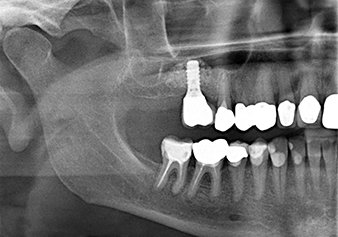

Lo strumento I2A (diametro 2,0 mm) è stato quindi impiegato per perforare il pavimento sinusale in modo graduale e su superfici molto ridotte. Tale metodo piezochirurgico previene il danneggiamento della membrana di Schneider. Durante l'utilizzo di Z25P, la membrana risultava già essere leggermente sollevata dal fluido di raffreddamento fornito attraverso la punta dello strumento (Fig. 3). La quantità di fluido di raffreddamento presente era solo del 50% per evitare che la sede dell'impianto registrasse un'elevata pressione.